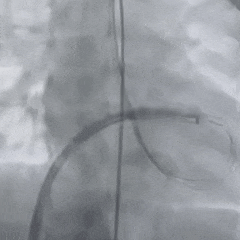

术中造影

术中造影复测缺损左室面破口3.9mm,隧道长11.37mm,判定为长隧道型室间隔缺损。

轨道建立

在肺动脉内圈套导丝,建立动静脉轨道